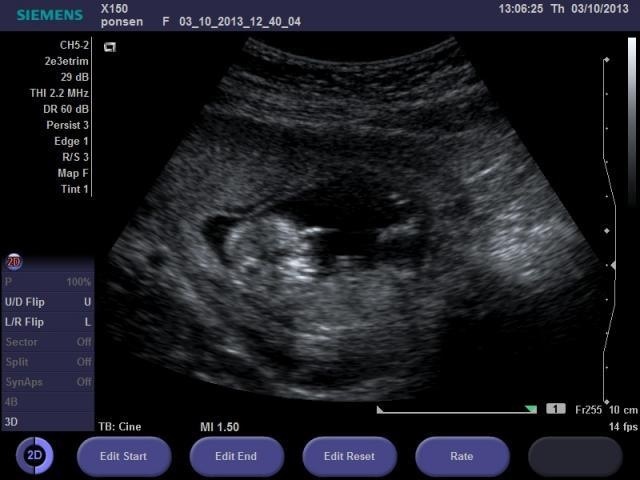

This is my ultrasound, taken yesterday, 12w5d.